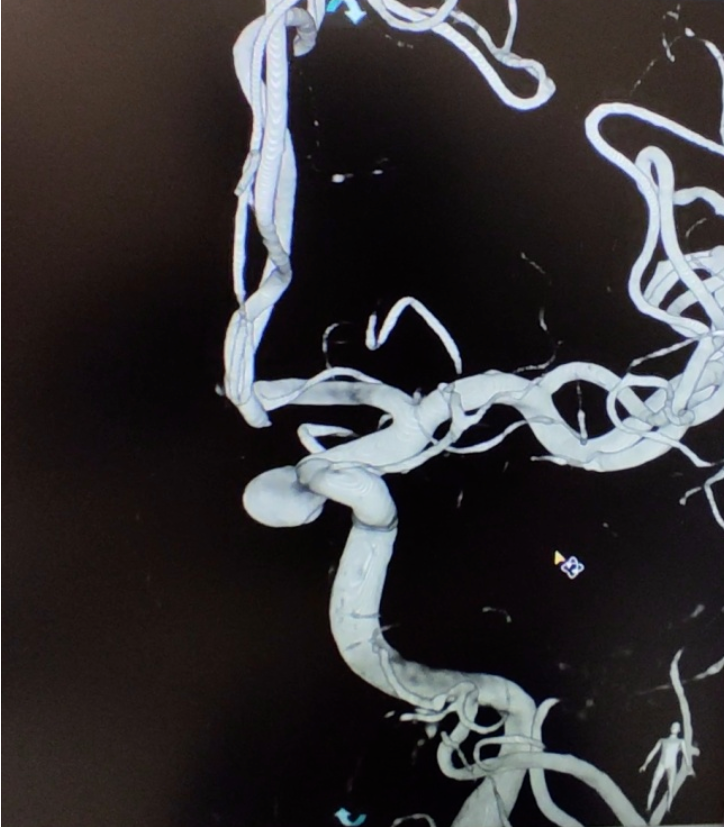

紅色箭頭提示頸內動脈床突段動脈瘤